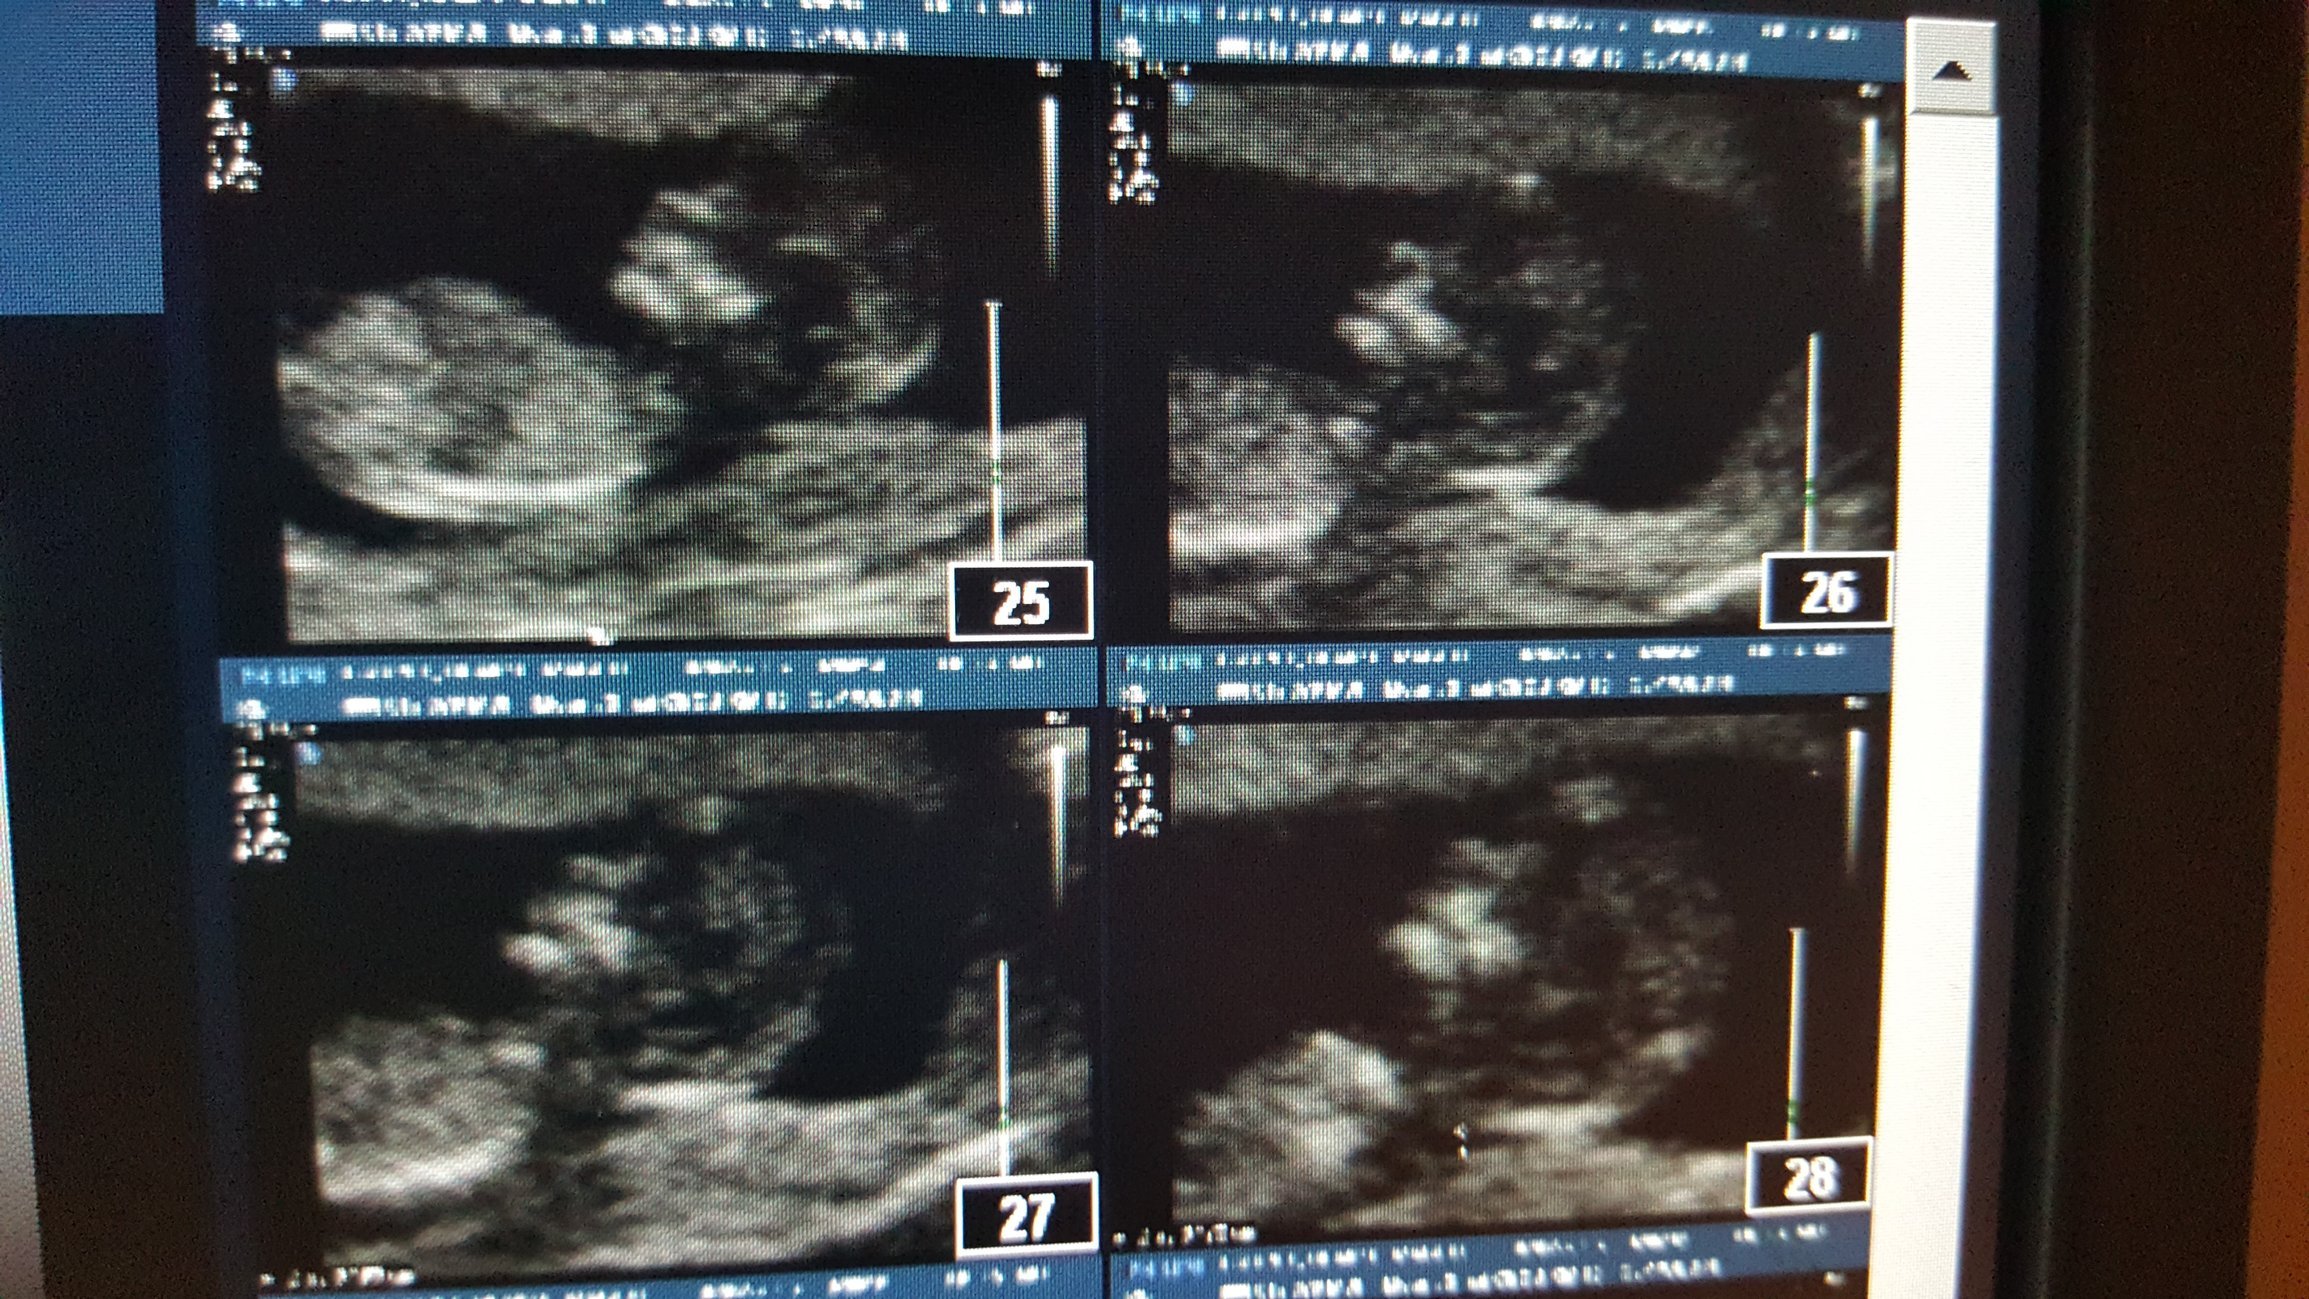

12w on the dot HR 167. Little stinker wouldn't sit still so the U/S took over an hour for the NT, and they ended up going from the external to internal U/S. Hey, you won't see me complaining that I got to watch the baby wiggle around for over an hour! Sorry the pics are so huge- I snapped a pic with my phone after cropping out my info